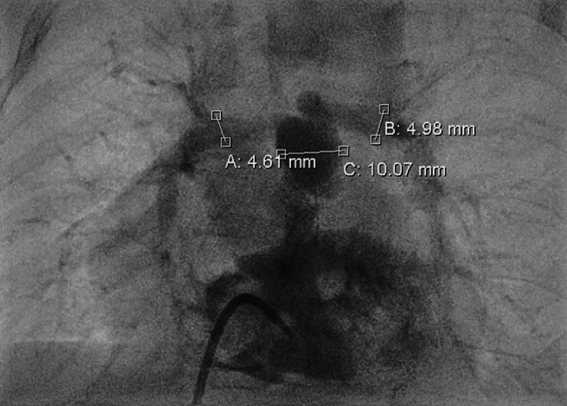

A 4-month-old infant (weight 5.2 kg, BSA 0.29 m2, oxygen saturation 84%) suffering from Tetralogy of Fallot (TOF), was referred for complete surgical repair at our institution. Diagnosis was made postnatally for development of cyanosis after birth. No comorbidities were present. Echocardiography showed a severe form of TOF with hypoplastic and dysplastic pulmonary valve of 3.5 mm of diameter with minimal anterograde blood flow and hypoplastic pulmonary branches of 2 mm of caliber. Continuous infusion of prostaglandin E was started, but urgent catheterization was needed because of progressive worsening of hypoxemia. A 6 mm stent was inserted in the right ventricular outflow tract (RVOT) (Fig. 1), with subsequent improvement of blood oxygenation, which allowed exstubation and home discharge. At the age of 4 months, the child underwent preoperative catheterization, which demonstrated good positioning of the previous stent, the pulmonary trunk of adequate caliber (10 mm), the right pulmonary artery (PA) of 4.6 mm, the left PA of 5 mm, and absence of severe stenoses in distal pulmonary branches (Fig. 2). Nakata index was 151 mm2/m2. After multidisciplinary evaluation, the patient was scheduled for complete surgical correction. Surgery was carried out on cardiopulmonary bypass (CPB). For RVOT reconstruction, a transannular homograft monocusped valve extended to the main pulmonary artery (MPA) was adopted (due to pulmonary valve entrapment in RVOT stent), the malaligned ventricular septal defect (VSD) was patch closed through a right atrial incision, the foramen ovale was left open. Pulmonary arteries (PAs) were probed and accepted a 5 mm Hegar. No intervention on PAs was performed. Extubation was possible on day 10th after resolution of transient right ventricular (RV) dysfunction due to junctional ectopic tachycardia and acute kidney injury requiring peritoneal dialysis. Postoperative echocardiography showed good reconstruction of MPA, but severe pulmonary regurgitation, and mild hypoplastic distal pulmonary branches. The patient was transferred to the ward on day 13th and maintained on prophylactic unfractionated heparin (UFH) 10 U/kg/h until right jugular central venous line removal on day 15th. The subsequent postoperative course was regular, with improving clinical status and nearly complete normalization of blood exams (see Table 1). On day 24th the patient presented sudden circulatory collapse requiring veno-arterial extracorporeal membrane oxygenation (VA-ECMO). Echocardiography showed severe RV dysfunction and absent blood flow through the right PA. Urgent diagnostic cardiac catheterization showed lack of contrast staining of the right PA suggestive of thrombosis (Fig. 3). Percutaneous thrombus fragmentation with multiple balloon dilations, local thrombolysis (Urokinase 4000 U/kg over 20 min), and aspiration were performed with partial thrombus removal and hemodynamic improvement. Continuous Urokinase infusion was not performed due to recent VA-ECMO cannulation. Following heart-team discussion, the patient was referred for surgical thrombus removal and concomitant central PAs enlargement plasty (Video 1): on CPB, MPA was transected and two thrombi were removed adopting the Fogarty technique (Fig. 4). Neither signs of intimal damage nor macroscopic focal arterial stenoses were noticed. Proximal right and left PAs enlargement plasty with heterologous pericardial patches was carried out (Fig. 5). An additional 3.5 mm opening was performed at the VSD patch. The patient was weaned from VA-ECMO easily in the operating room. Right ventricular function recovered gradually, with left-to-right shunting at the calibrated VSD, and estimated RV pressure equal to half of the systemic. Blood exams showed an isolated moderate increase in factor VIII activity and a slight decrease in factor IX and XI activity (see Table 1). Most frequent prothrombotic genetic polymorphisms were excluded (Leiden V factor and G20210A prothrombin gene mutation) and common inherited severe thrombophilia was ruled out (see Table 1). During hospital stay he was maintained on UFH increased to 20 U/kg/h and discharged home one month later on Warfarin (target INR 2-3) for six months, after hematological consultation. One-month control cardiac magnetic resonance revealed satisfactory PAs reconstruction and no thrombi were detected. Currently, the patient is in good clinical status and he had no relapse of thrombosis after discontinuation of anticoagulation therapy.

Fig. 2 Preoperative catheterization demonstrating the pulmonary trunk of 10 mm, the right pulmonary artery of 4.6 mm, the left pulmonary artery of 5 mm, and absence of stenoses in distal pulmonary branches